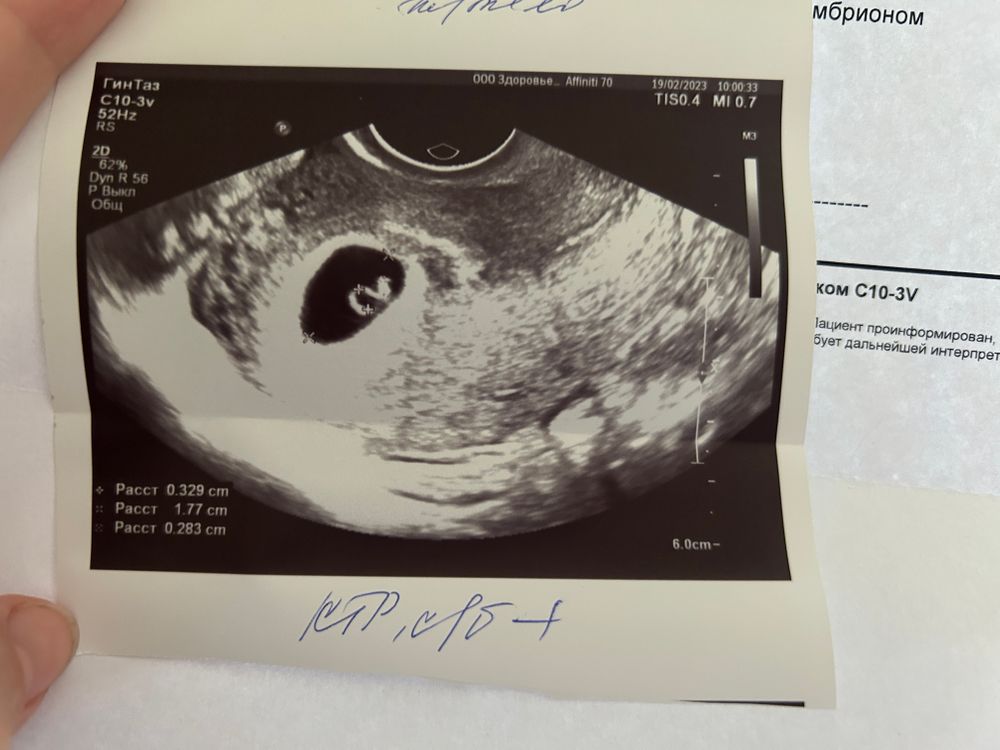

Меня смущает разница между плодным яйцом и ктр. Само плодное яйцо опережает мой срок, ктр в рамки вроде вписывается.